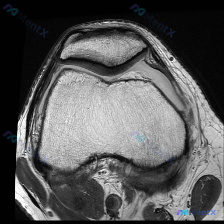

今天看到一个很有代表性的读片问题,整理出来和大家分享讨论:问题是判断这张髌股关节轴位T1加权MRI上有没有软骨异常,我们一步步梳理思路。

这是一张膝关节MRI的轴位T1加权图像,扫描层面位于膝关节上方的髌股关节层面:

- 骨骼结构:髌骨位于前方,骨皮质边缘清晰,骨髓脂肪信号正常;股骨滑车形态正常,骨皮质连续,骨髓信号均匀,没有局灶性信号异常。

- 关节软骨:髌骨后方及股骨滑车表面的关节软骨厚度均匀,形态规则,没有看到明确的局灶缺损或者信号异常,也没有看到明确的软骨剥脱征象。

- 周围软组织:髌前、髌下脂肪垫信号均匀;股内侧肌、股外侧肌形态正常,髌骨周边支持带结构清晰;关节腔内没有明显异常积液,滑膜也没有增厚。

- 对位关系:髌股关节对位良好,没有明显髌骨脱位或半脱位。

- 从这张T1图像本身,没有发现支持软骨异常的明确证据,髌骨和股骨滑车软骨的形态、厚度、信号都没有明显异常。

- 但这里有个很关键的点:影像没有发现异常≠真的没有病变,T1序列本身对软骨病变的敏感度很低,假阴性概率很高。

这张单张轴位T1图像上,髌股关节结构大致正常,没有看到明确的软骨异常信号,但因为T1序列本身的局限性,绝对不能就此排除软骨病变,尤其是早期软骨软化。临床怀疑和影像结果不符的时候,一定要先质疑影像的技术局限性,而不是否定临床判断,这是很多年轻医生容易踩的陷阱。